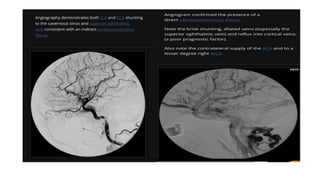

• Angiography (DSA)

-Rapid shunting from ICA to CS

-Enlarged draining veins

-Retrograde flow from CS, most commonly into the ophthalmic veins

Radiographic features • CT: -ProptosisEnlarged superior ophthalmic veins -Extraocular muscles may be enlarged -Orbital oedema -May show SAH/ICH from a ruptured cortical vein • Angiography (DSA) -Rapid shunting from ICA to CS -Enlarged draining veins -Retrograde flow from CS, most commonly into the ophthalmic veins • Ultrasound Arterialised ophthalmic veins may be seen on Doppler study

DSA a.Digital angiogram ofcarotid circulation confirming carotid-cavernous fistula b. Digital angiogram of vertebral circulation showing right ophthalmic vein ingurgitated. C.Digital angiogram with final image after treatment of the traumatic CCF